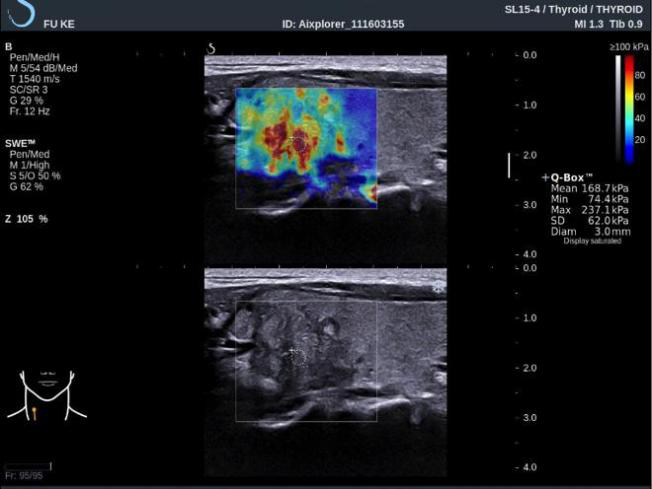

▲甲状腺乳头状癌:E 成像显示结节内部硬度明显增高达到 237.1kPa,且软硬不均。